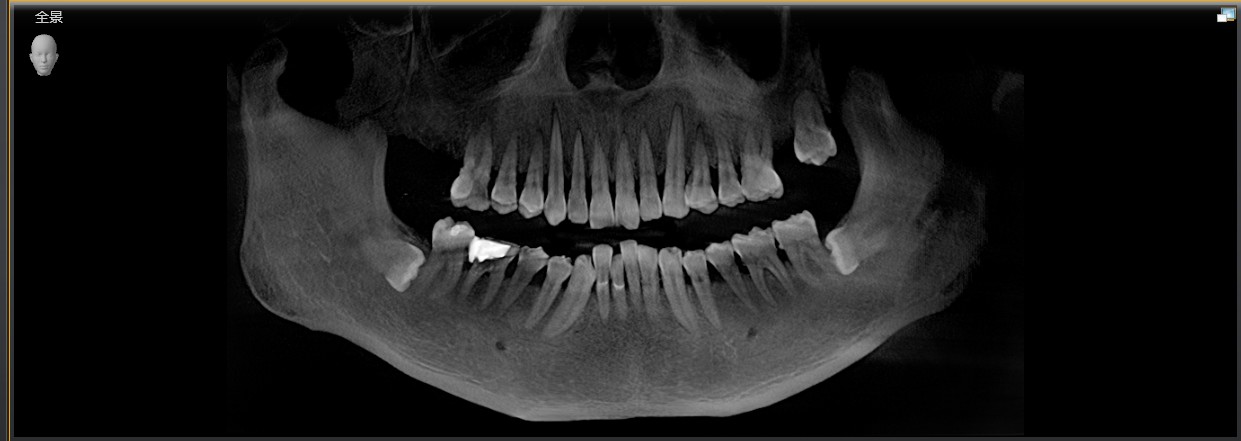

患者是成功人士,平时非常忙碌,忽略了口腔健康,直到有一天无法咀嚼食物后才想到要治疗牙齿,我们为他摄了CBCT,发现有重度牙周病,上合双侧7自然脱落,左上8,III度松动,并近中倾斜移位,对合牙严重伸长,还有其他牙齿疾患,需要综合治疗;经过牙周病治疗、上合窦骨增量、上合种植修复、拔牙、截冠、根管治疗、桩冠、高嵌体修复等!时间长达一年,终于恢复了正常牙列!可以享受食物的美好!